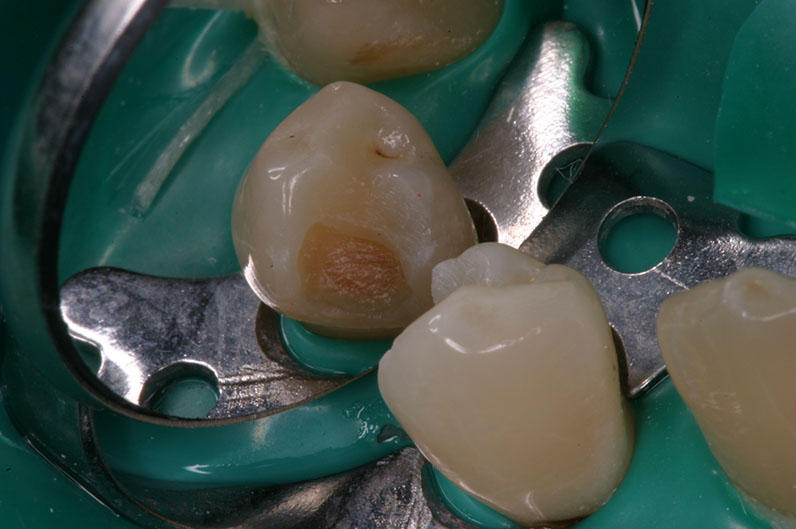

Dopo lo scavo

con Facelight